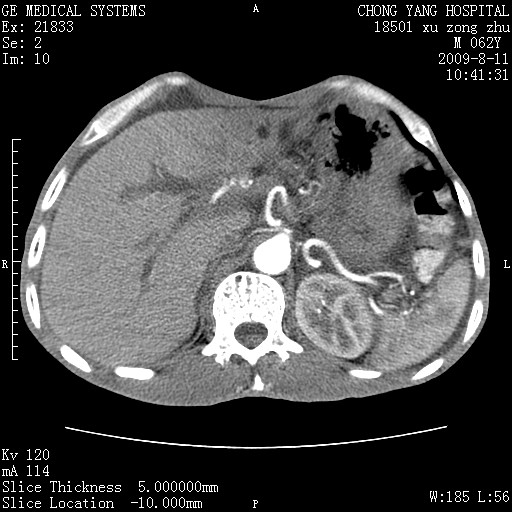

以下是引用杀毒软件在2009-8-11 16:35:00的发言:[br]肝内胆管扩张局限于左叶,胆管内有结石伴肝外胆管结石,胆管壁增厚呈弥漫性并发腹腔积液,胰腺边界模糊。[br][br]考虑---胆总管及肝内胆管结石继发胆管炎及胰腺炎,左肾下极囊肿,腹水。

以下是引用zjzjr在2009-8-11 17:35:00的发言:[br]肝内胆管扩张局限于左叶,胆管内有结石伴肝外胆管结石,胆管壁增厚呈弥漫性并发腹腔积液。[br][br]考虑---胆总管及肝内胆管结石继发胆管炎,左肾下极囊肿,腹水。